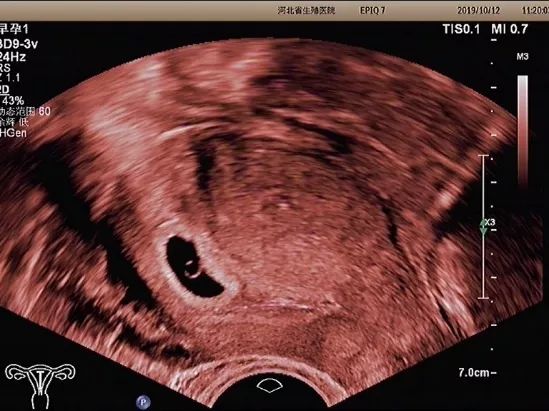

妊娠囊

确定妊娠囊是否在宫腔内,妊娠囊在宫腔内的位置、数目及大小。妊娠囊的大小可随孕周增长而增长。

卵黄囊

卵黄囊是妊娠囊内超声能发现的第一个解剖结构。当超声发现卵黄囊,即可以确定妊娠。正常的卵黄囊直径约3~8mm,卵黄囊过大、过小或不显示及变形均提示妊娠结局不良。

胚芽

可根据胚芽长度评估孕周,有无心管搏动,确定胚胎是否存活。